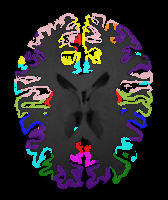

Moving Target Mono-0 Mono-21 DA-1 DA-21 Mono-65 Refer to caption Refer to caption Refer to caption Refer to caption Refer to caption Refer to caption Refer to caption Refer to caption Refer to caption Refer to caption Refer to caption Refer to caption Refer to caption Refer to caption

Image Manual Seg DA-1 Mono-5 DA-5 Mono-200 Refer to caption Refer to caption Refer to caption Refer to caption Refer to caption Refer to caption

Figure 4: Examples of brain MRI registration (top) and knee MRI segmentation (bottom) results. Top: The first two columns are the moving image/segmentation and the target image/segmentation followed by the warped moving images/segmentations by different models. Bottom left to right: original image, manual segmentation, and predictions of various models. Mono-i𝑖i and DA-i𝑖i represent the mono- and DA models trained with i𝑖i manual segmentations respectively.